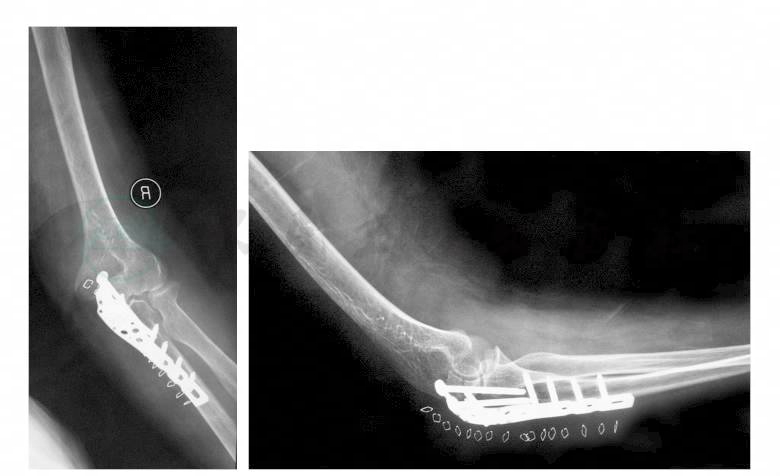

术后第1日,嘱患者开始患侧腕及手的主动活动,术后第2日拔除引流管。术后复查X线片见骨折部位复位及固定良好,未见松动、断裂及移位(图2)。

图2 术后肘关节正侧位X线片